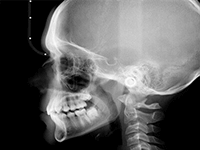

Pro Patient: Our state-of-the-art cone-beam computed tomography (CBCT) technology could selectively image the sinus, oral maxillofacial, para-nasal sinuses, ear & throat regions.

The aforementioned technology is inherent in the “myRay X9 CBCT Scan” that we use. myRay X9 is an Italian-made Oral Maxillofacial CT-Scan, certified compliant by European, Japan, USA and other international authorities in radiation safety.